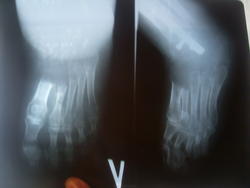

Мне 30 лет из Беларуси. В 2008г. во время беременности появились боли в стопе. После рождения ребёнка рентгенснимок показал образование в области пяточной кости. Была сделана биопсия. Заключение онкологов-фиброзная дисплазия без морфологических признаков малигнизации. Направлена к ортопедам-травматологам, они с диагнозом ФД не согласились, поставили остеосаркома под?. Была сделана повторная биопсия в онкологии, заключение то же ФД. Ортопеды-травмотологи Беларуси отказались меня лечить, операцию по удалению кости и эндопротезированию выполняли в онкологии. Гистология после операции показала ФД. Через год происходит рецидив в таранной кости. Биопсия в онкологии показывает ФД. Далее операции выполняют в России, Петербург по удалению таранной кости и её замещению. Через год происходит 2 рецидив. В данный момент мне не могут поставить диагноз. Онкологи ставят ФД, в ЦИТО зав.патологанат.отд поставил остеосаркому низкой степени злокачественности, некоторые травматологи по снимкам считают, что это прогрессирующий остеолиз (Gorham Stout disease). Как говорится кто болше? Что по снимкам скажете ВЫ?![]()

3. 2 рецидив с поражением костей предплюсны, дистальной части болшой берцовой кости. Фиброзная дисплазия без морфологических признаков малигнизации. (2011г.)